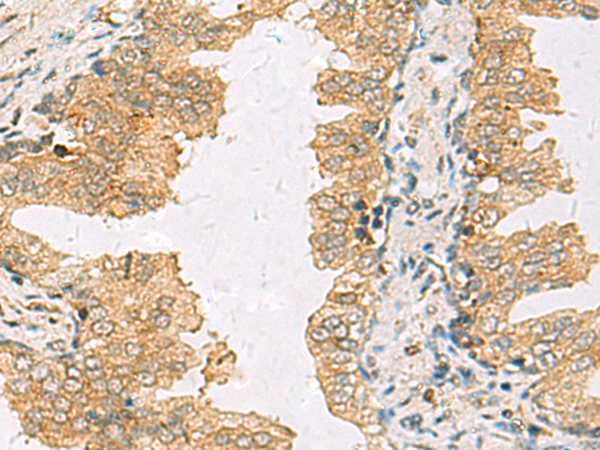

分类: 科研抗体货号: P03308别名: HYPA; FBP11; FLAF1; FNBP3; HIP10; Prp40; FBP-11; HIP-10; NY-REN-6应用: WB,IHC反应种属: Human, Mouse